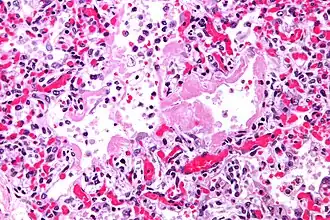

La progression rapide des symptômes initiaux à l'insuffisance respiratoire est une caractéristique clé. Le diagnostic s'appuie sur une tomodensitométrie (TDM) permettant d'écarter les autres causes de lésion aigüe du poumon[3]. Une biopsie du poumon qui montre l'organisation de lésions alvéolaires diffuses peut aussi être pratiquée. D'autres tests de diagnostic sont utiles pour exclure d'autres conditions similaires, mais l'histoire, la radiographie et la biopsie sont essentielles. Ces autres tests peuvent inclure des analyses sanguines de base, des hémocultures et un lavage bronchoalvéolaire.

_Idiopathic_DAD_2.jpg)

_Idiopathic_DAD.jpg)